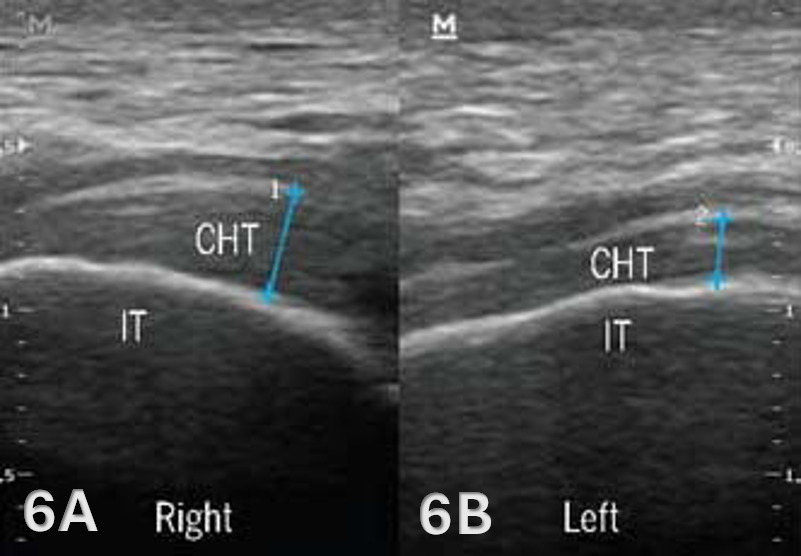

The starting point for examining the proximal hamstring tendon and muscle is at the osseous landmark – the ischial tuberosity.12,13,17–19 The ischial tuberosity can almost always be palpated, giving the examiner a perfect location to begin their scan. The proximal hamstring can be scanned in both the long axis (LAX) and the short axis (SAX). In the LAX view, depending on the probe width and size, one should start proximally to visualize the hyperechoic reflection of the bony cortex of the ischial tuberosity, with its large acoustic shadow underneath. In LAX, the proximal hamstring tendon fibers of the long head of the biceps femoris and the semitendinosus conjoint tendon should be easily seen coming off the attachment of the ischial tuberosity with a clear hyperechoic fibrillar structure running distally from the insertion site on the anterior lateral origin of the ischial tuberosity. The semitendinosus fibers can be easily seen as they reach the ischial tuberosity directly. Lateral to the hamstring muscle complex, the sonographer will see the sciatic nerve that appears as a fascicular, flattened structure that descends between and deep to the long head of the biceps femoris and semimembranosus tendon.1 The probe can be turned 90 degrees for viewing in the SAX. If the probe is moved slightly distally in the SAX view, the biceps femoris will appear as a triangular shape. As the examiner moves distally along the biceps muscle belly, the size will decrease until it appears to disappear. In both views, some toggling may be required to reduce anisotropy.

Transducer Type: Because of the depth of the proximal hamstring tendon and muscle, a standard high-frequency, linear array transducer between 5-15 MHz is normally utilized. However, in some individuals with more adipose tissue or larger muscle mass, depth may require a lower-frequency curvilinear probe to obtain depth.10,15,16